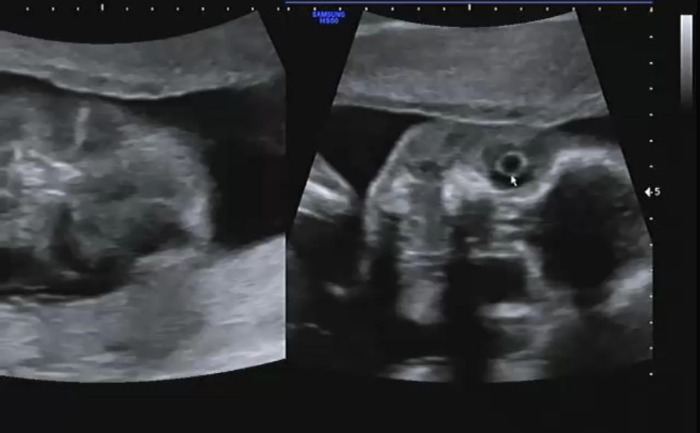

복부를 보고 장기가 주수에 맞게 잘 발달하고 있는지 확인했다. 심장, 간, 위 등 현재 잘 있는지 확인하고 심장에서 혈류가 잘 흐르고 있는지 확인했다. 심장이 심실 2, 심방 2로 잘 나뉘어 있는지 혈류가 알맞게 흐르고 있는지 확인하는데 신기했다. 혈류가 알맞게 제 방향으로 흐르는 것을 확인하고 태아의 심장이 잘 뛰고 있는지 확인했다.